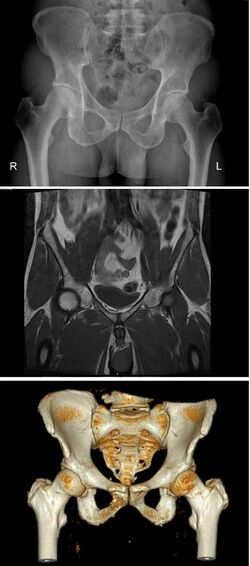

Diameters of pelvic inlet

Pelvic girdle anatomy